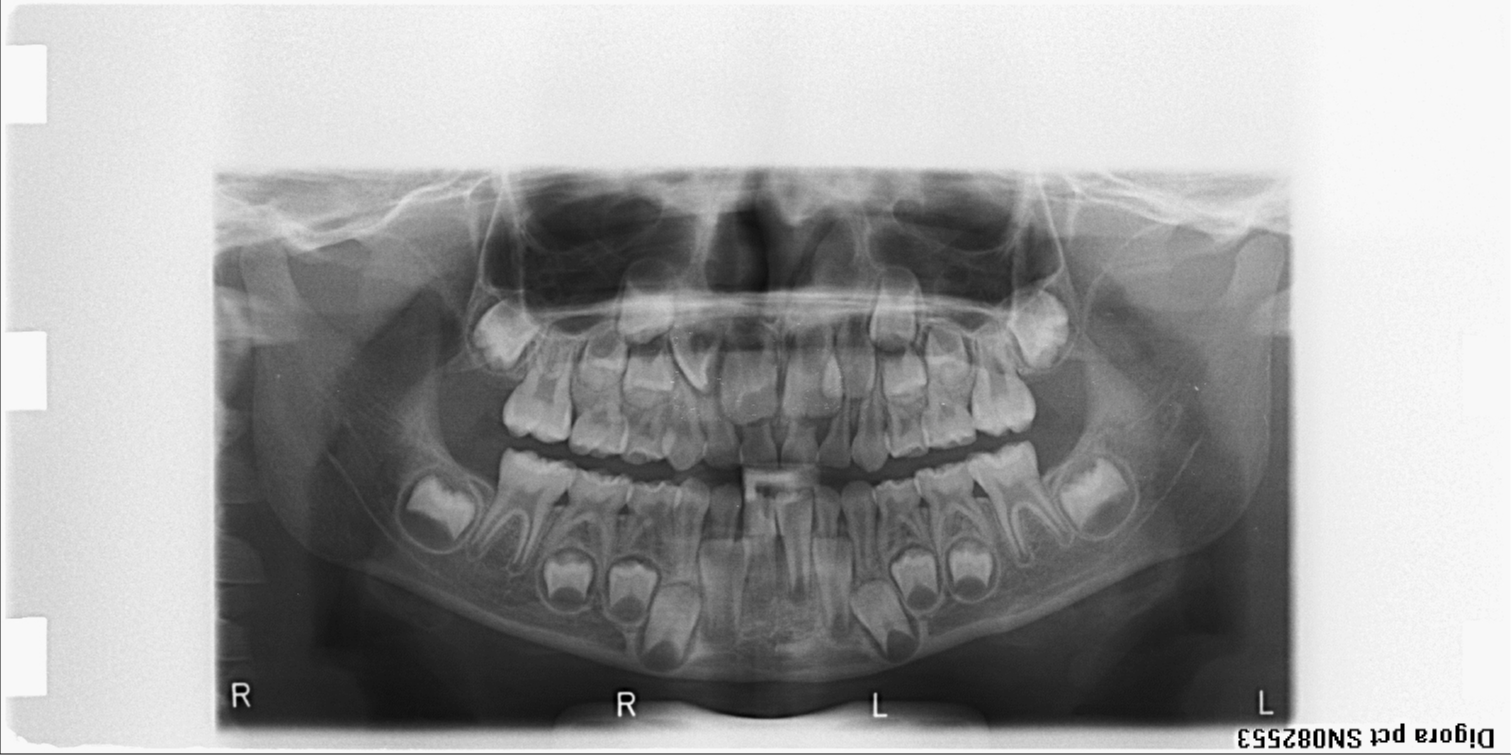

bilan des radiographies début et fin de traitement